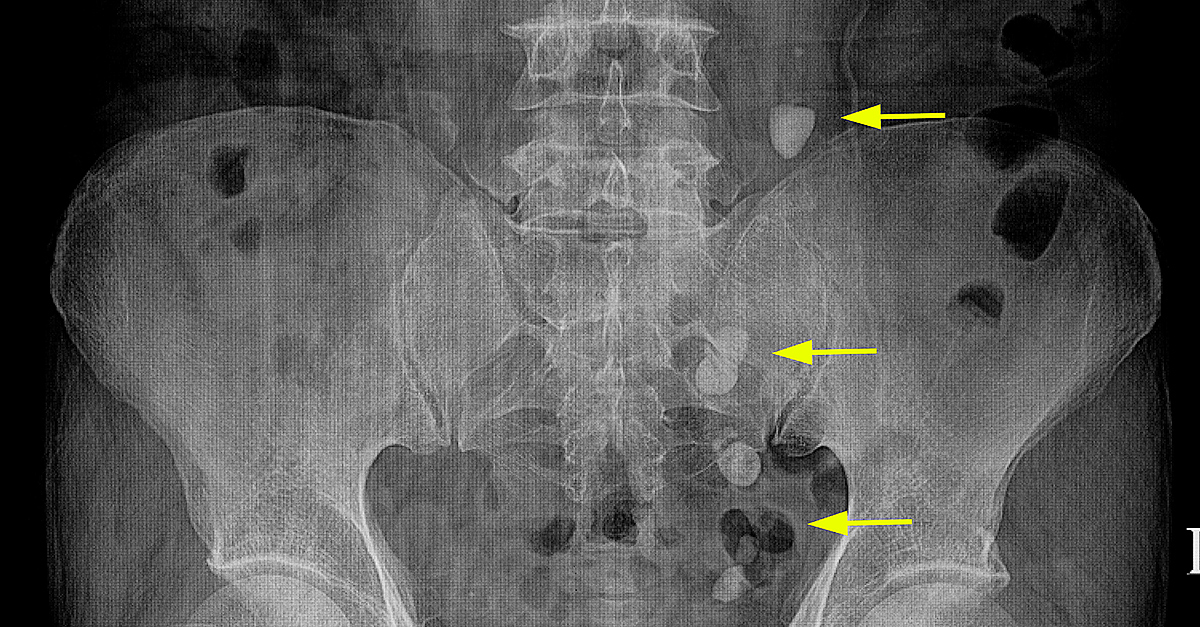

If a patient goes to the ER, a doctor who suspects stones often does some form of imaging, such as a CT scan or an ultrasound of the kidney with an X-ray, to confirm their presence, Bechis said. A CT (computed tomography) scan can help pinpoint the location of stones and is useful in determining the exact size and shape. Bechis also mentioned the availability of low-dose CT scans that emit low levels of radiation.

Canvasser said imaging via CT scans is the most common method for diagnosing ureteral stones.